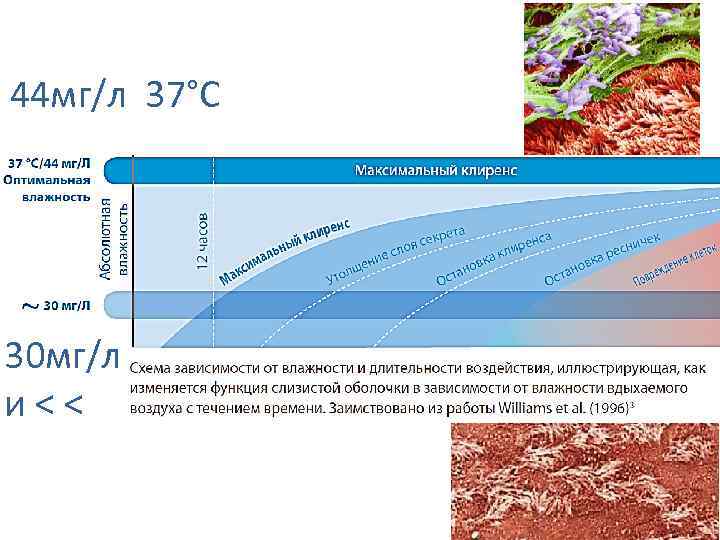

44 мг/л 37°С 30 мг/л и < <

44 мг/л 37°С 30 мг/л и < <

Факторы риска : Недостаточное увлажнение дыхательной смеси При длительной ИВЛ (> 24 ч) Мы используем только увлажнители испарительного типа

Факторы риска : Недостаточное увлажнение дыхательной смеси При длительной ИВЛ (> 24 ч) Мы используем только увлажнители испарительного типа

44 мг/л 37°С 30 мг/л и < < 24 ч

44 мг/л 37°С 30 мг/л и < < 24 ч